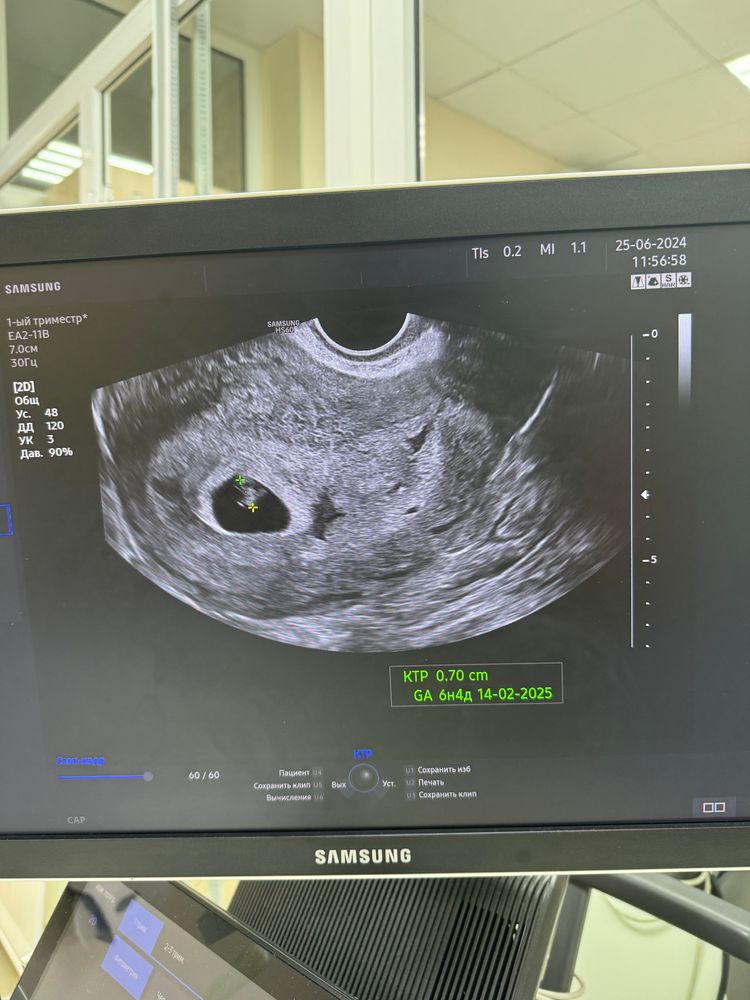

УЗИ ровно 7 недель и 7 мм малыш(ка)

А по размеру определили, что это 6+4, а не 7.